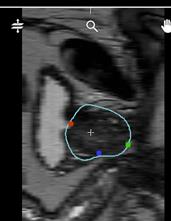

How to check: When the DICOM volume is displayed on the "Contour" page, the volume is displayed inverted on the apex-base axis. The position of the bladder is an effective reference point: "on the left", the volume is displayed correctly, "on the right", the volume is displayed inverted.

| Image displayed correctly: the bladder is on the left | Image displayed reversed: the bladder is on the right |